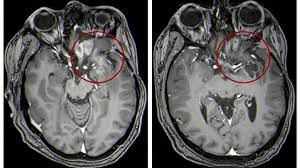

When you have a child with cancer, social media can provide a wonderful lifeline of support. Having your child diagnosed with a terminal brain tumour is one of the most devastating and terrifying things that can happen to any parent. If the tumor affects the optic pathway, which is responsible for sight, the child may experience vision changes. A seizure is sometimes the first sign of a brain tumor, but it can happen at any stage. This is partly because pressure in the brain increases when you're lying down, and a tumor can make that worse. Children of any age may be affected. When claire was sick i used caring bridge to communicate updates to the myriads of supportive people who were following her story throughout treatment. This way you will be able to address questions that your child may have about your cancer diagnosis. Brain tumors, either malignant or benign, are tumors that originate in the cells of the brain. Many children with a brain tumor experience headaches before their diagnosis. For most children, you do not need to go into a lot of detail about side effects. There are new and better drugs and treatments, and we can now also work. As the tumor grows, it creates pressure on and changes the function of surrounding brain tissue, which causes signs and symptoms such as headaches, nausea and balance problems.

Brain tumors, either malignant or benign, are tumors that originate in the cells of the brain. Early diagnosis and intervention is key. Problems speaking clearly, swallowing, or walking If the tumor affects the optic pathway, which is responsible for sight, the child may experience vision changes. One red flag to watch out for:

Opinion Andrew Kaczynski My Baby Daughter Died Of Brain Cancer Here S What We Can Do To Save Other Kids The Washington Post from arc-anglerfish-washpost-prod-washpost.s3.amazonaws.com The types of brain tumors are based on the cell type and location in the brain. Brain tumours are the most common tumours that develop in children. A brain tumor can form in the brain cells (as shown), or it can begin elsewhere and spread to the brain. Problems speaking clearly, swallowing, or walking Boys are affected slightly more often than girls. Your child may have any of the following: Most seizures in children are not caused by brain tumors, but if your child has a seizure, your child's doctor may refer you to a neurologist (a doctor who specializes in brain and nervous system problems) to make sure it wasn't caused by a brain tumor or other serious disease. Headaches, which may become more frequent and more severe feeling of increased pressure in the head unexplained nausea or vomiting